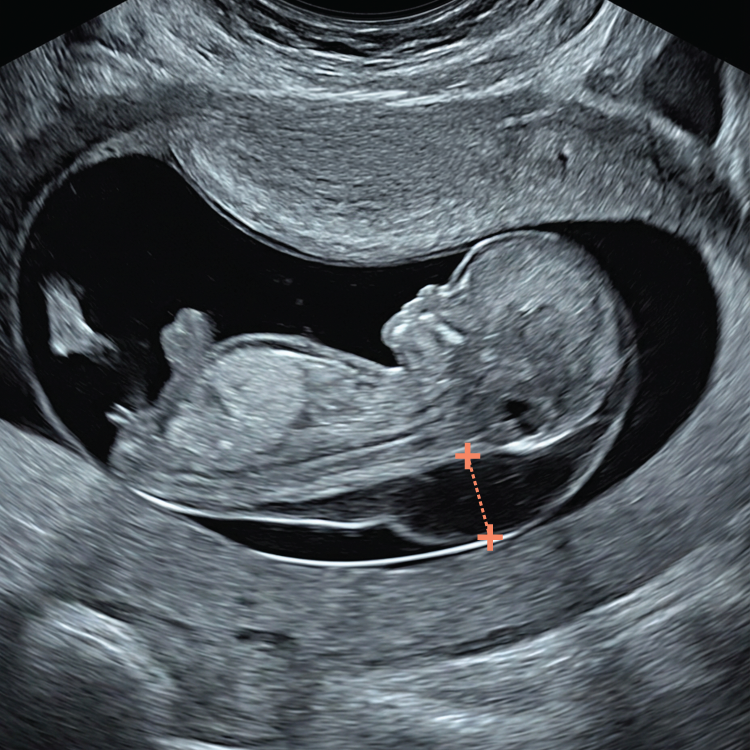

You simply cannot apply the classic 11–14-week NT rules to a 10-week fetus, which is why we developed specific 10-week NT criteria. At 10 weeks the fetus is smaller, has different proportions and is structurally less mature than at the standard 12-week scan.

This becomes especially important when you are trying to measure a significantly increased NT. You cannot zoom in to a strict “head–chest” view as recommended later in the first trimester, because the whole fetus will not fit the screen and excessive magnification makes the NT borders blurred and difficult to measure accurately. At 10 weeks the fetus is also missing some key landmarks used later, such as the nasal bone.

Using a CRL-type sagittal image rather than a classic NT-type view optimises workflow, reduces scanning time and fetal exposure, and frees more time to assess vital structures such as the brain and spine.